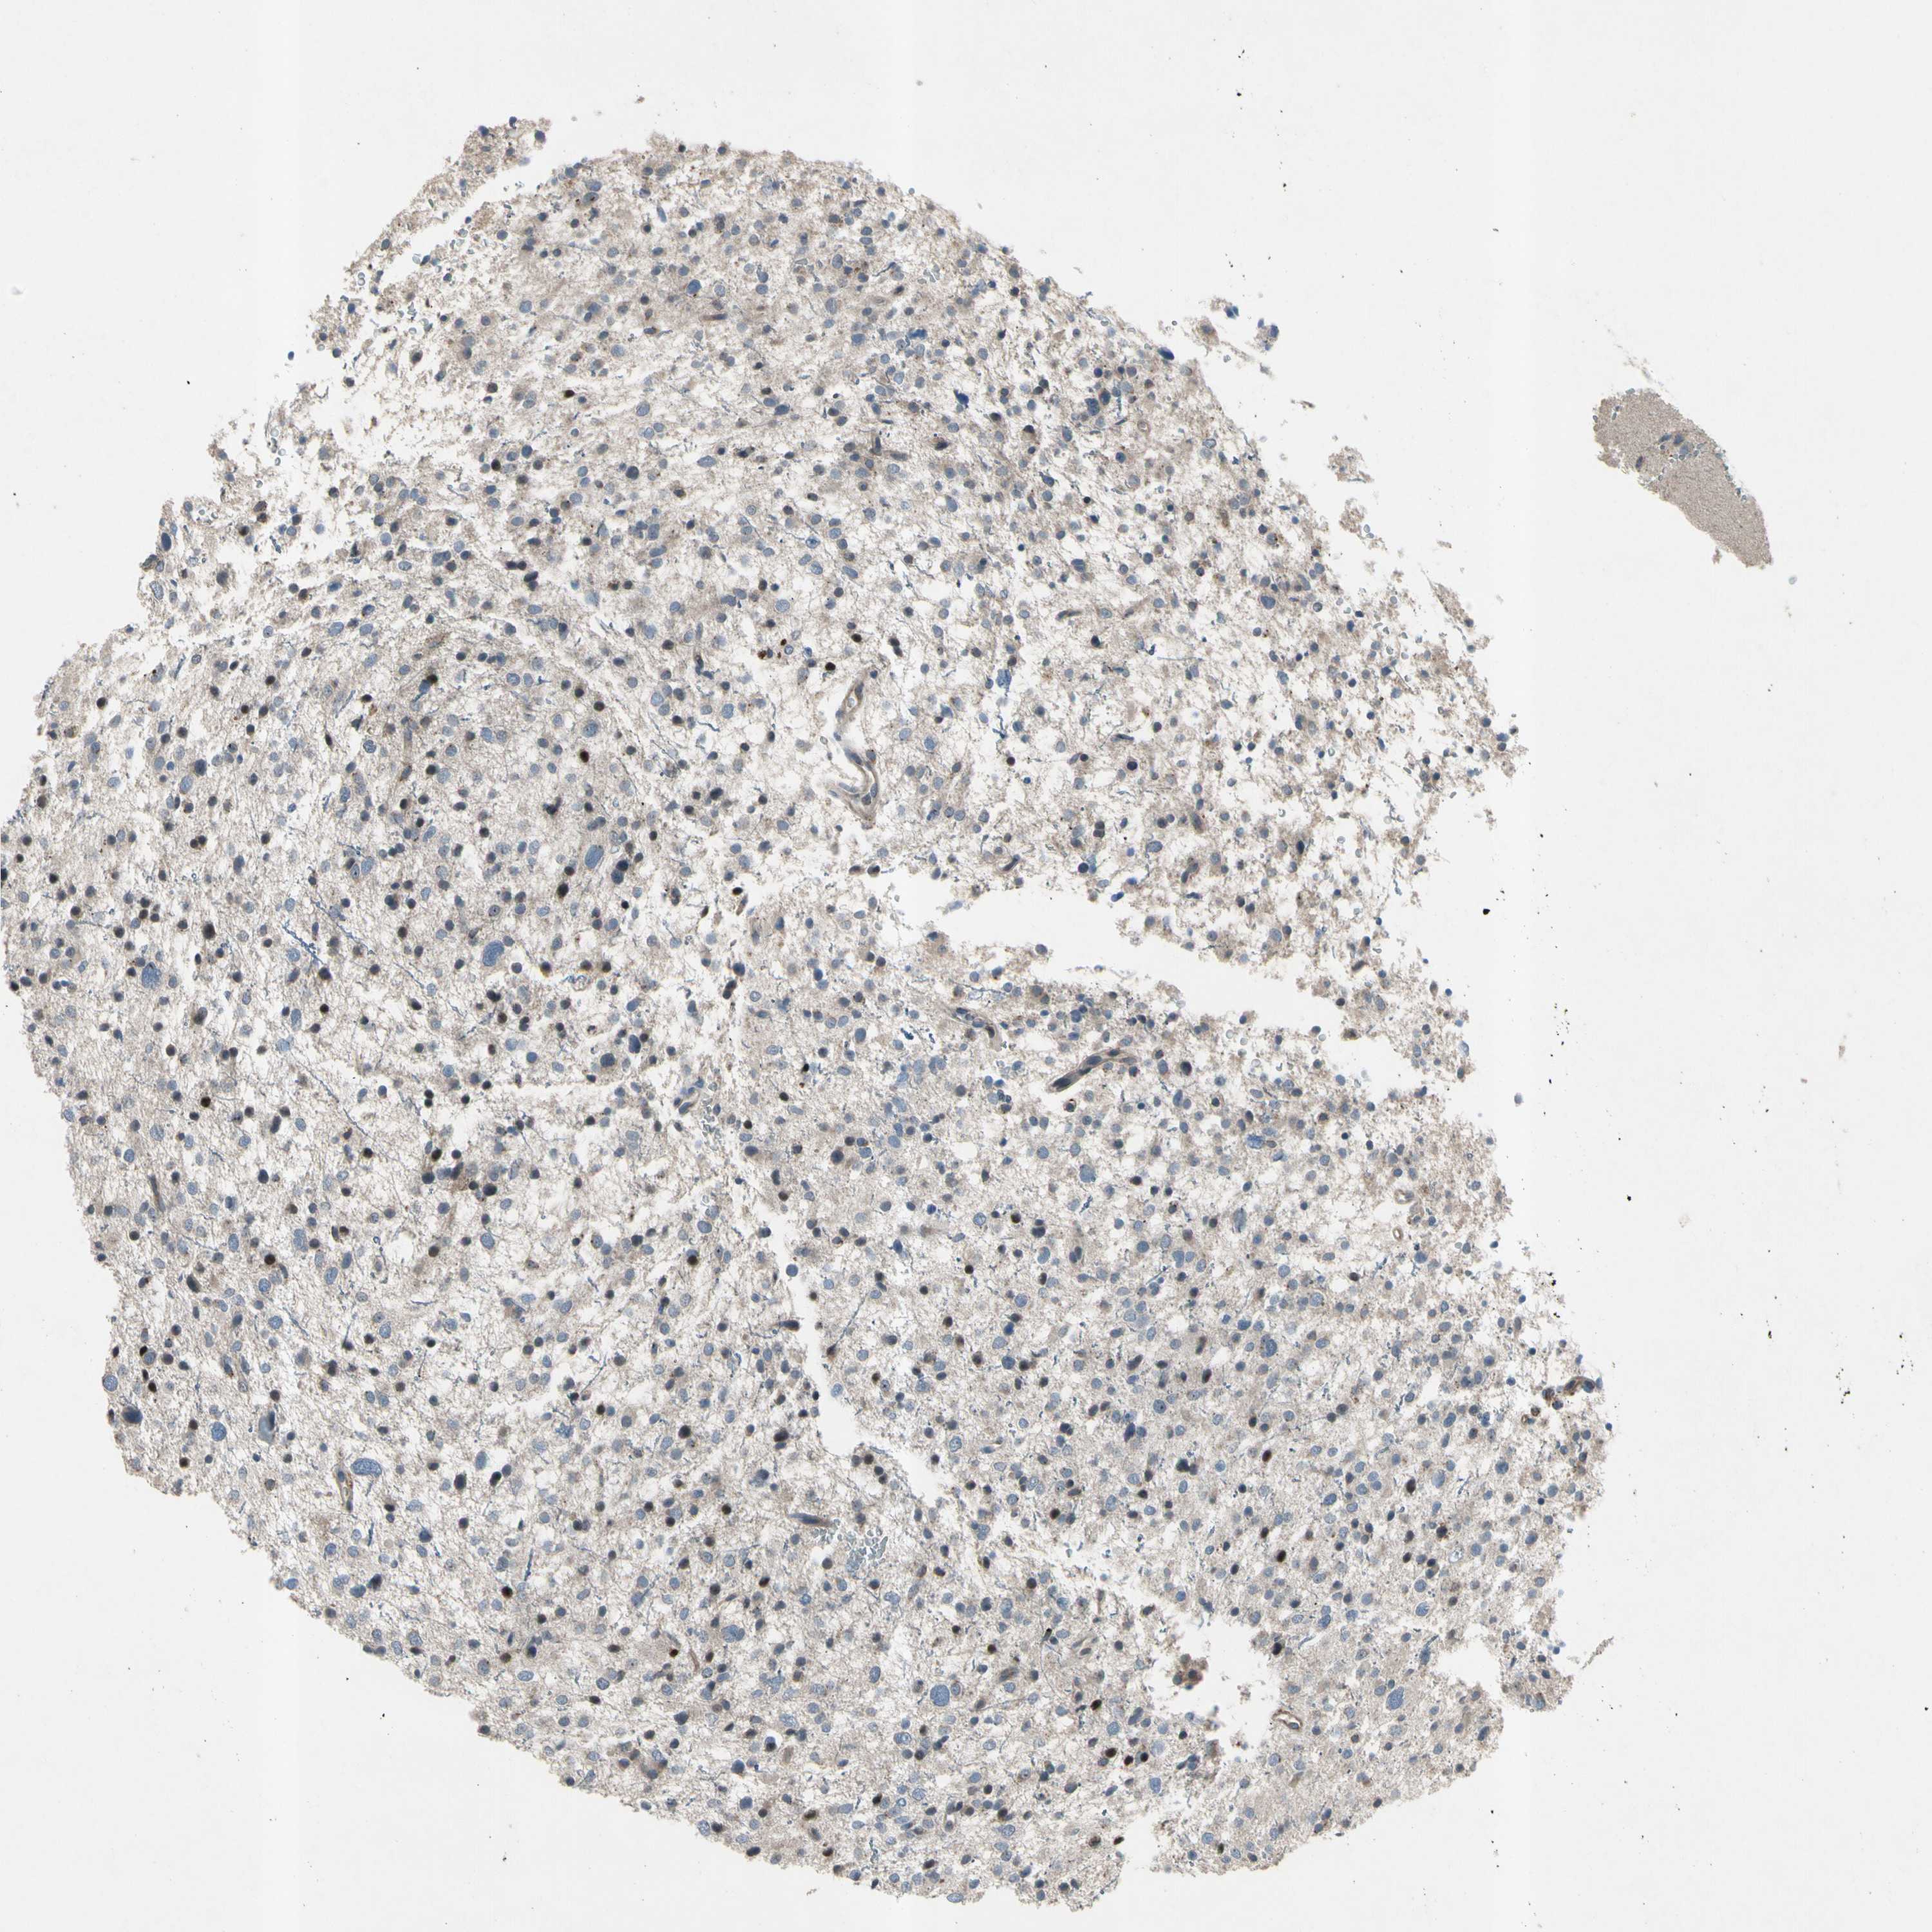

GLIOMA - Protein expressioni

A mouse-over function shows sample information and annotation data. Click on an image to view it in a full screen mode. Samples can be filtered based on level of antibody staining by selecting one or several of the following categories: high, medium, low and not detected. The assay and annotation is described here.

Note that samples used for immunohistochemistry by the Human Protein Atlas do not correspond to samples in the TCGA dataset.

Antibody stainingi

Antibody staining in the annotated cell types in the current human tissue is reported as not detected, low, medium, or high, based on conventional immunohistochemistry profiling in selected tissues. This score is based on the combination of the staining intensity and fraction of stained cells.

Each image is clickable and will lead to virtual microscopy that enables deeper exploration of all samples and also displays staining intensity scores, fraction scores and subcellular localization as well as patient and tissue information for each sample.

Antibody HPA008588

Staining

High

Medium

Low

Not detected

Intensity

Strong

Moderate

Weak

Negative

Quantity

>75%

75%-25%

<25%

None

Location

Nuclear

Cytoplasmic/membranous

Cytoplasmic/membranous,nuclear

Glioma, malignant, High grade

Glioma, malignant, Low grade